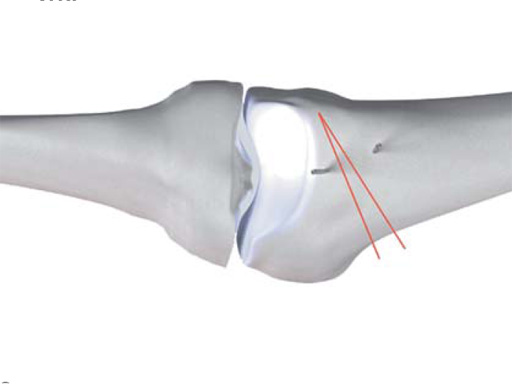

Distal femoral varus osteotomyThe goal of distal femoral varus osteotomy is to shift the mechanical leg axis from the lateral to the medial compartment. There are various possibilities for surgical correction of valgus malalignment. Open wedge lateral osteotomy or dome osteotomies of the distal femur have been widely used in recent years. Unfortunately, local complaints occurred in many cases mostly caused by the fixation methods (ie, frequent irritations of the iliotibial tract and loss of correction). Therefore new improved surgical technique based on an incomplete medial closing wedge osteotomy with an internal plate fixator was developed.

An anteromedial skin incision is used. This skin incision can be reused and expanded during subsequent knee surgery. The vastus medialis muscle is dissected from the septum, the medial patellofemoral ligament (MPFL) and the distal insertion of the vastus medialis muscle are partially incised. Two blunt Hohmann retractors are placed around the distal femur. The oblique osteotomy starts in the medial supracondylar area and ends in the lateral condyle, approximately 10 mm inside the lateral cortex. For guiding the closing wedge osteotomy of the distal femur a specific saw guide will be available soon. Alternatively, it is possible to use K-wires inserted under image intensifier control to mark the bone cuts. The saw cuts are made with retractors protecting the soft tissue and vessels. The wedge is removed and the height and depth of the osteotomy can be measured. At this time it is possible to make modifications concerning the wedge size. Closing the wedge must be done gradually by gentle compression of the lower leg laterally, and stabilizing the knee joint medially near the area of osteotomy. This may take several minutes to enable plastic deformation of the lateral cortex to close the osteotomy gap. Leg alignment is checked radiologically after closing with a rigid alignment bar positioned between hip and ankle center. The bar representing the weight-bearing line should pass the preoperatively defined mechanical axis. The plate is inserted from distal under the vastus medialis muscle. The distal drill holes are oriented in a 20 angle inclination on the frontal plane to avoid a posterior perforation of locking head screws in the distal femur. The distal four bolts are placed. A lag screw is positioned in the dynamic hole directly above the osteotomy for compression of the osteotomy site. The screw should be tightened carefully using the image intensifier. The plate is now fixed to the shaft with bolts monocortically, and the lag screw is replaced by a bolt bicortically. The wound is closed in layers after insertion of a drain. The patient is mobilized on the first day after surgery. Partial weight bearing is recommended for 6 weeks, active movement of the knee is enhanced. Biomechanical testing confirmed superior stability of medial closing wedge techniques as compared to lateral open wedge techniques and favourable axial and torsional loading characteristics of the TomoFix medial distal femur (MDF) plate. The plate is now available, as well as a booklet on the operative technique.